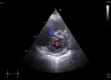

The diagnosis of atrial septal defect (ASD) may be delayed until adulthood or even later in life as it is a well-tolerated congenital heart disease. If patients are not examined and investigated well in childhood, the diagnosis may be delayed until later in adulthood when patients present with palpitations and sometimes dyspnea due to the right chambers dilatation from right ventricular volume overload. In this report, we present a case of a 50-year-old female patient with symptoms of heart failure and atrial fibrillation who was found to have dilated right cardiac chambers, dilated pulmonary artery, severe tricuspid regurgitation, pulmonary hypertension, and a pulmonary-to-systemic flow ratio (Qp/Qs) of more than 1.5 by transthoracic echocardiography and Doppler, indicating left to right shunt at the atrial level. However, transthoracic echocardiography could not visualize the defect, and two-dimensional (2D) transesophageal echocardiography was done in this patient and documented the presence of a sinus venosus ASD with an incomplete cor triatriatum dexter membrane; all four pulmonary veins were identified going to the left atrium. Since the presence of an incomplete cor triatriatum dexter membrane (despite causing no symptoms) makes the percutaneous closure of the sinus venosus ASD and the percutaneous repair of tricuspid regurgitation very difficult, we decided to advise surgical ASD closure and tricuspid valve repair for the patient.